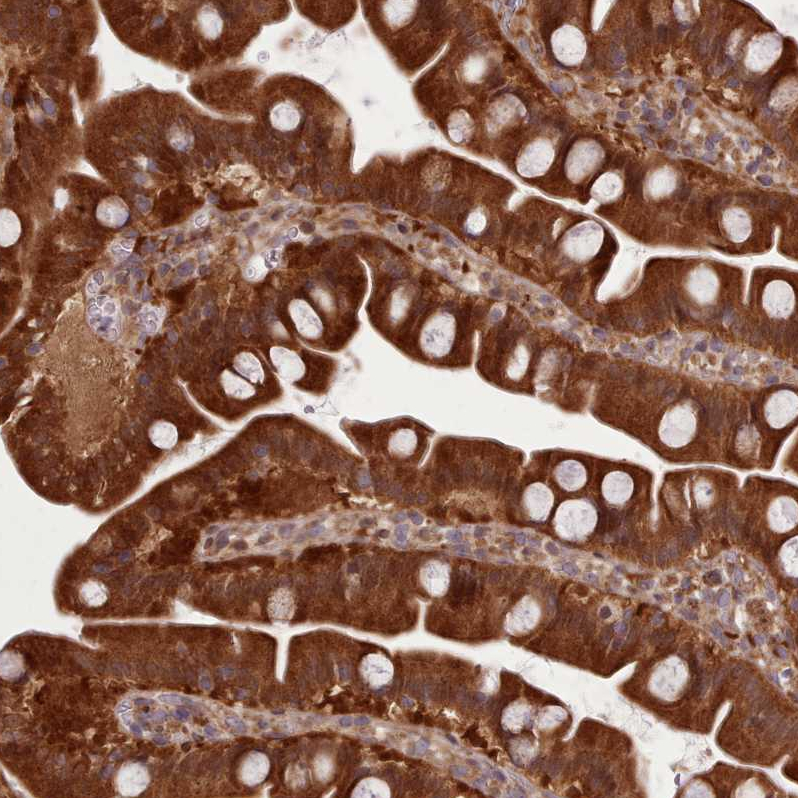

Immunohistochemical staining of human kidney shows strong cytoplasmic positivity in cells in tubules.